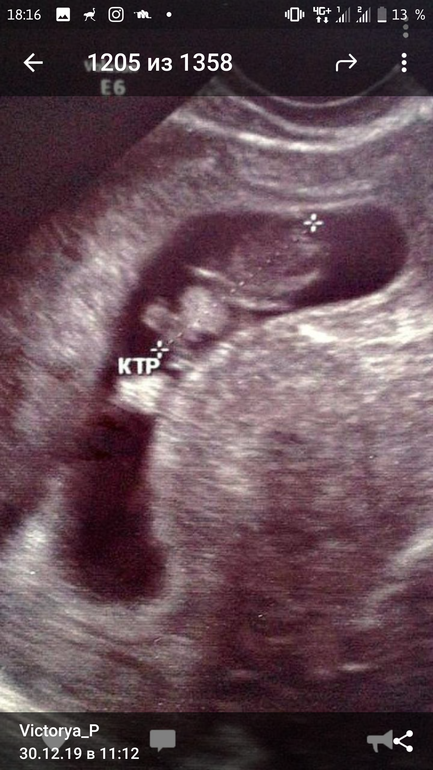

Просто я четко знаю когда была овуляция и день зачатия. На узи вообще не очень большое плодное. 7 мм. А хгч такой

На узи одно плодное 7 мм.